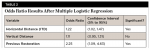

Horizontal distance from the implant platform/abutment connection to the adjacent tooth: The data indicates that as the distance between the natural tooth and the implant increases, the incidence of decay increases precipitously (Figure 2 and Figure 3). Decay occurrences range from 7.4% when the implant-tooth distance (ITD) is <2 mm to 40% when the ITD is ≥6 mm. In the 69 sites that exhibited caries, the mean ITD was 4.1 mm, and in the 338 sites without decay the mean ITD was 3.5 mm (P = .005) (Table 1). A logistic regression was performed with the single binary variable indicating whether or not the "horizontal threshold distance" was greater than 4 mm. The results show a statistically significant odds ratio of 2.00 (95% confidence interval of 1.191599, 3.350288) (Table 2.) Therefore, it is suggested that the horizontal threshold of 4 mm be considered as the "critical ITD."

Vertical distance from the interproximal contact area to the implant platform: This measurement varied greatly among samples and showed not to be a statistically significant contributing factor in decay formation (Table 2).

Presence or absence of restorations on the adjacent teeth: A positive correlation between existence of a previous restoration and decay was found (Figure 4, Figure 5, and Table 2).

This study strongly suggests that there is a direct correlation between the horizontal ITD and incidence of decay. The 17% incidence (range = 7.4% to 40%) of caries formation on the 407 sites was significantly higher than normal incidence of root caries (1.87% to 2.7%) previously reported in the literature.2,3 It can be inferred from this data set that an ITD of <4 mm is recommended to significantly reduce the likelihood of developing caries in teeth adjacent to molar implants. Additionally, the data suggests a statistically significant correlation between the presence of a previous restoration on the natural tooth and caries formation. However, this data should be considered with caution as not all decay occurred directly at the restorative margin, but rather some decay occurred distant to the margin, further apically on the root surface.